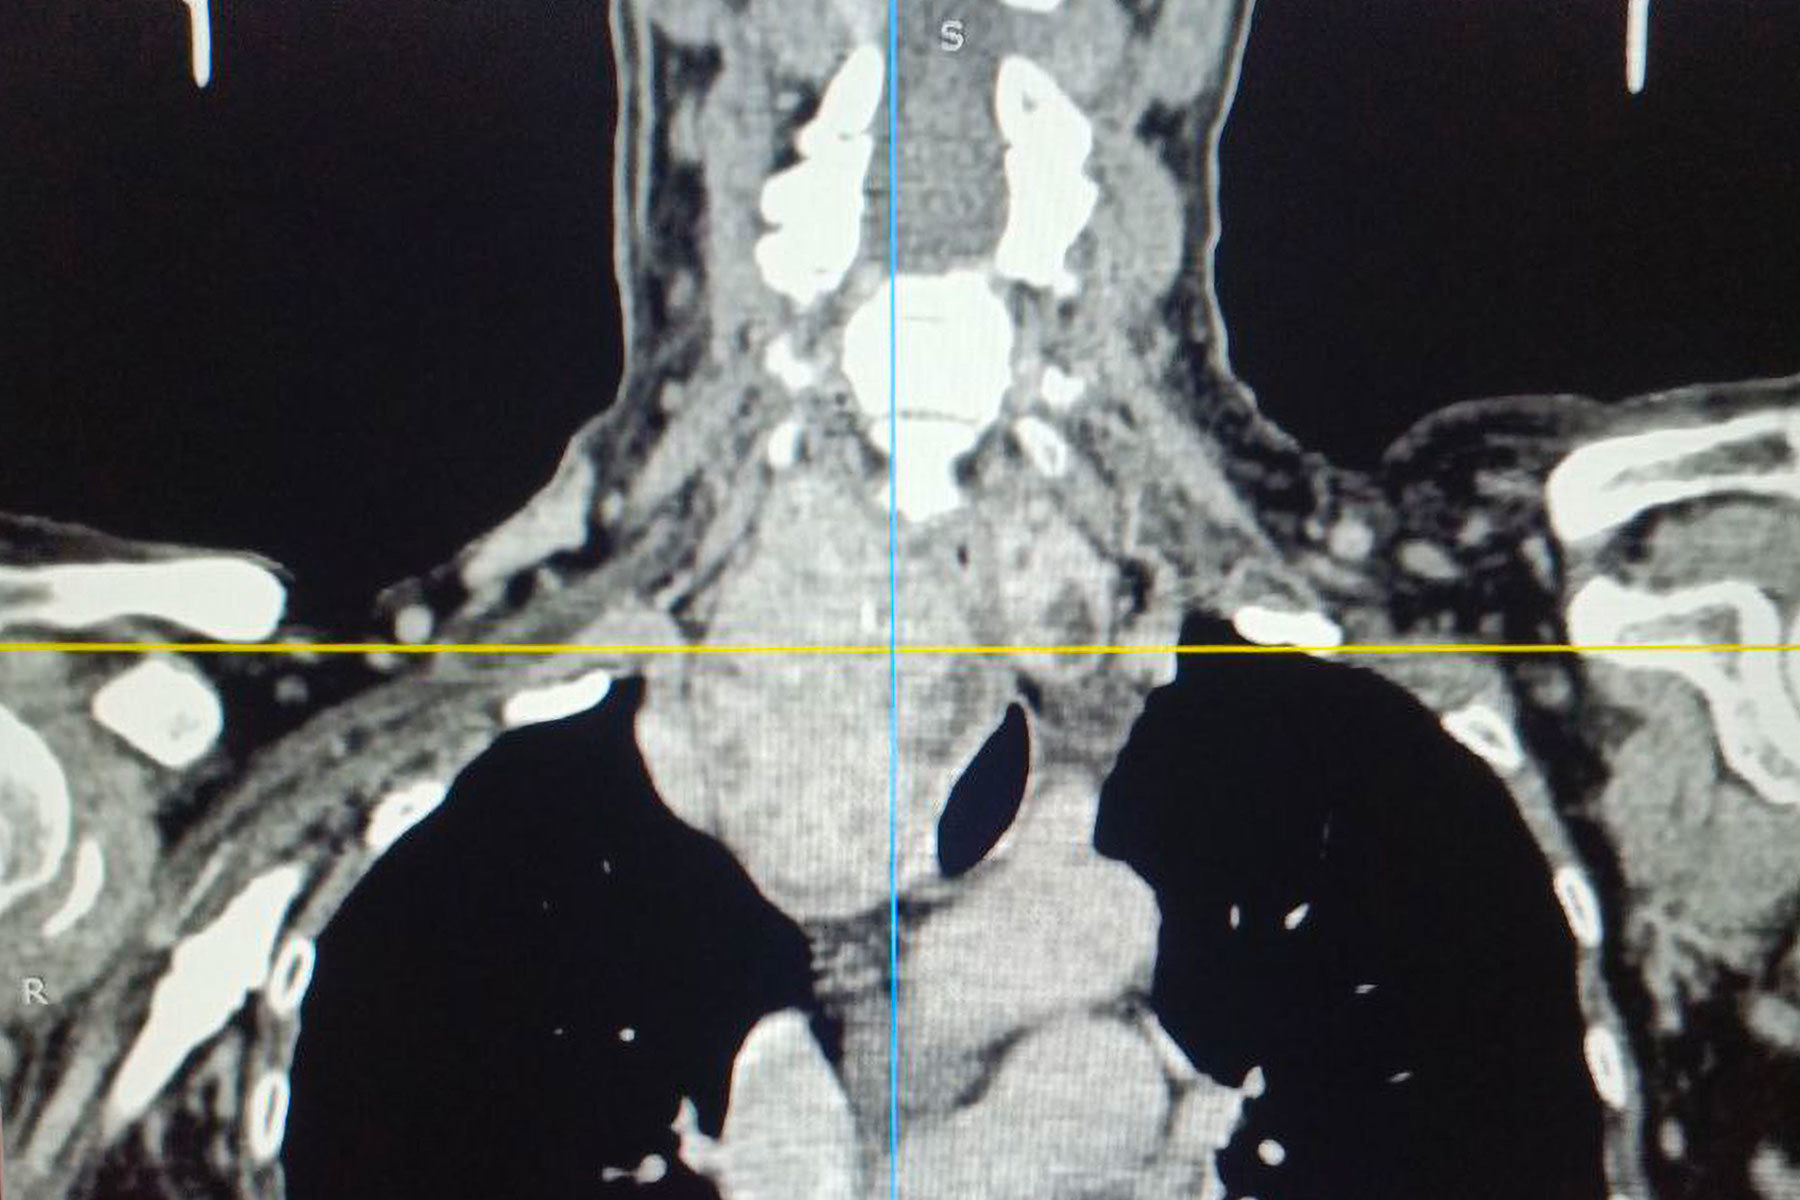

Операции предшествовало комплексное обследование, включавшее компьютерную и

Особую сложность представляло анатомическое расположение зоба. По словам хирурга, расположение зоба было частично загрудинным, образование опускалось за грудину примерно на две трети. А правая доля щитовидной железы подходила вплотную к плечеголовному стволу — крупному артериальному сосуду. Кроме того, зоб циркулярно охватывал трахею, сдавливая ее со всех сторон и вызывая у пациентки затруднение дыхания даже при небольшой физической нагрузке.